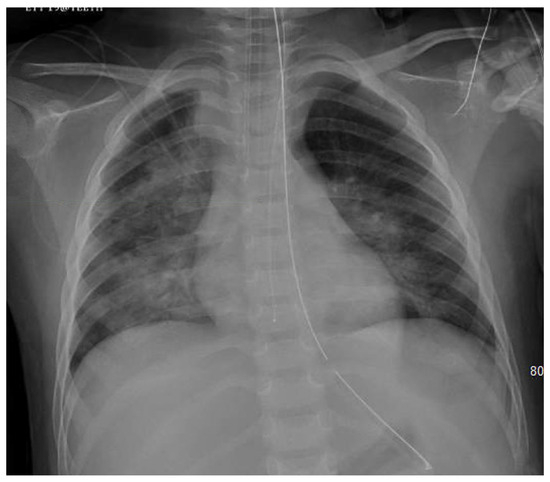

| CXR | Cardiomegaly, interstitial edema, dilated pulmonary artery, pleural effusion, alveolar edema, Kerly lines | Easily obtained/good initial screening Lacks sensitivity and specificity | |